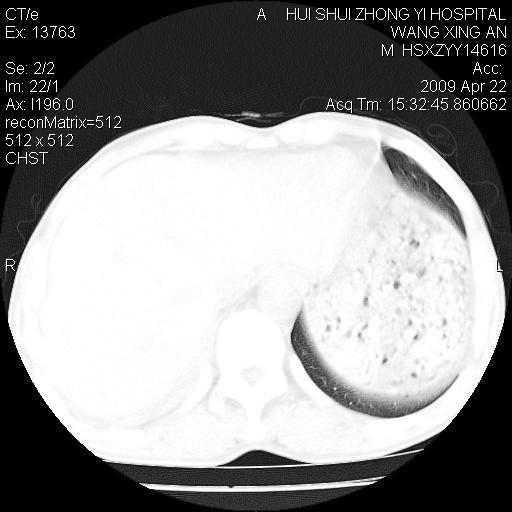

标题: CT19534:患者男、46岁咳嗽、胸痛半月。 [打印本页]

标题: CT19534:患者男、46岁咳嗽、胸痛半月。

1、右下肺中央型肺癌并右肺转移,右肺下叶不张。(肿块围绕右肺下叶支气管生长,致管腔闭塞右肺下叶不张;右肺有结节影)。

2、右侧胸腔积液。

3、右中上肺陈旧性肺结核(右肺见纤维化病灶及点状钙化)。

1、右下肺中央型肺癌并右肺转移,右肺中下叶不张。(右肺有结节影)。胸骨转移

2、右中上肺陈旧性肺结核(因为大多为纤维灶)。

3、右侧胸腔积液。